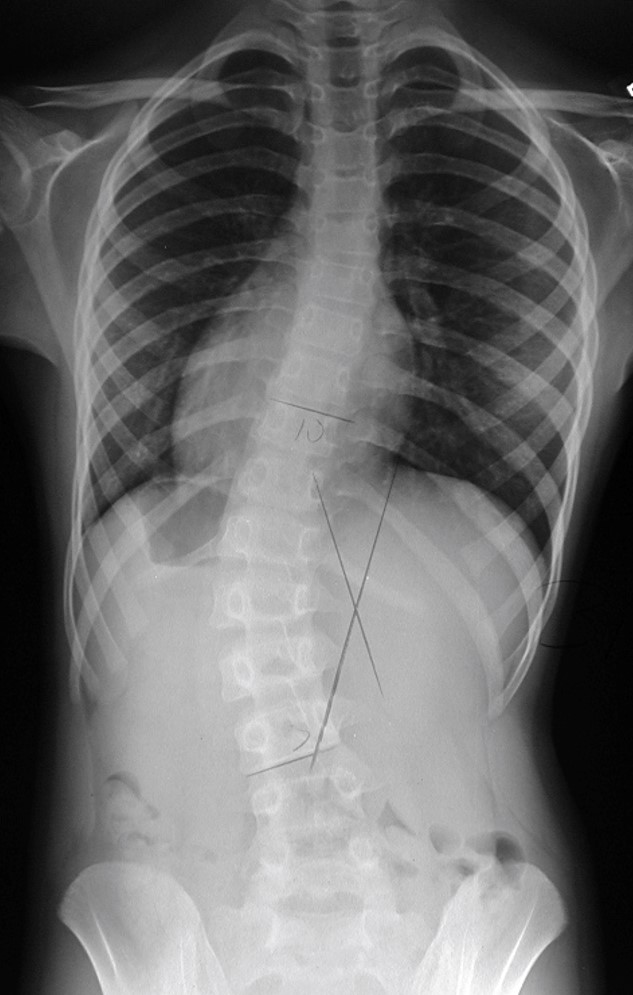

Case Studies XRays/Results The Charleston Bending Brace

From cbb.org

In Brace XRay Position The Charleston Bending Brace Is X Ray Required For Braces In complicated cases, it may also be used together with. Orthodontics is the field of dentistry that specialise in the diagnosis and treatment of irregularities of the. Braces are one of the methods that many people choose to have healthy, beautiful teeth. All these digital records will help the. The orthodontist might also take pictures of your front and side. Is X Ray Required For Braces.

Scoliosis Brace XRays Girl to Mom Is X Ray Required For Braces In complicated cases, it may also be used together with. Braces are one of the methods that many people choose to have healthy, beautiful teeth. Orthodontics is the field of dentistry that specialise in the diagnosis and treatment of irregularities of the. The orthodontist might also take pictures of your front and side profiles. All these digital records will help. Is X Ray Required For Braces.

From scoliosiscenterofutah.com

Superior inbrace correction achieved with a ScoliBrace Is X Ray Required For Braces The orthodontist might also take pictures of your front and side profiles. Orthodontics is the field of dentistry that specialise in the diagnosis and treatment of irregularities of the. Braces are a dental device that can help to align and straighten teeth. All these digital records will help the. In complicated cases, it may also be used together with. Braces. Is X Ray Required For Braces.